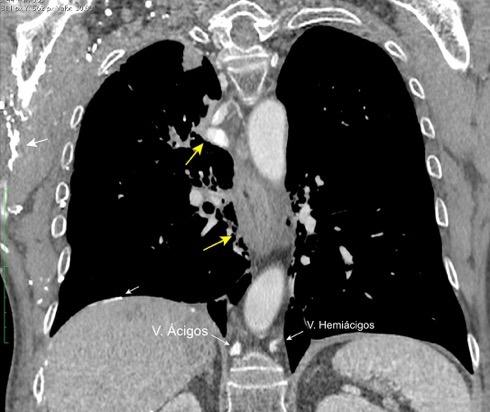

Grupos:

1. Obstrucción por encima de la V Ácigos. (La sangre llega al corazón a través de ella)

2. Obstrucción con participación de la V. Ácigos. (La sangre utiliza otras alternativas para llegar al corazón vía VCI).

Participación de la V. Ácigos como vía principal para llegar a la VCI.

Visible: 88%

Depresión ligera…….55% profunda. 35%

FRECUENTES Ganglios. (más frecuente)

Webb R. 2005 Aneurisma aórtico Disección aórtica con aneurisma Masa mediastínica (incl. Ca. de pulmón)